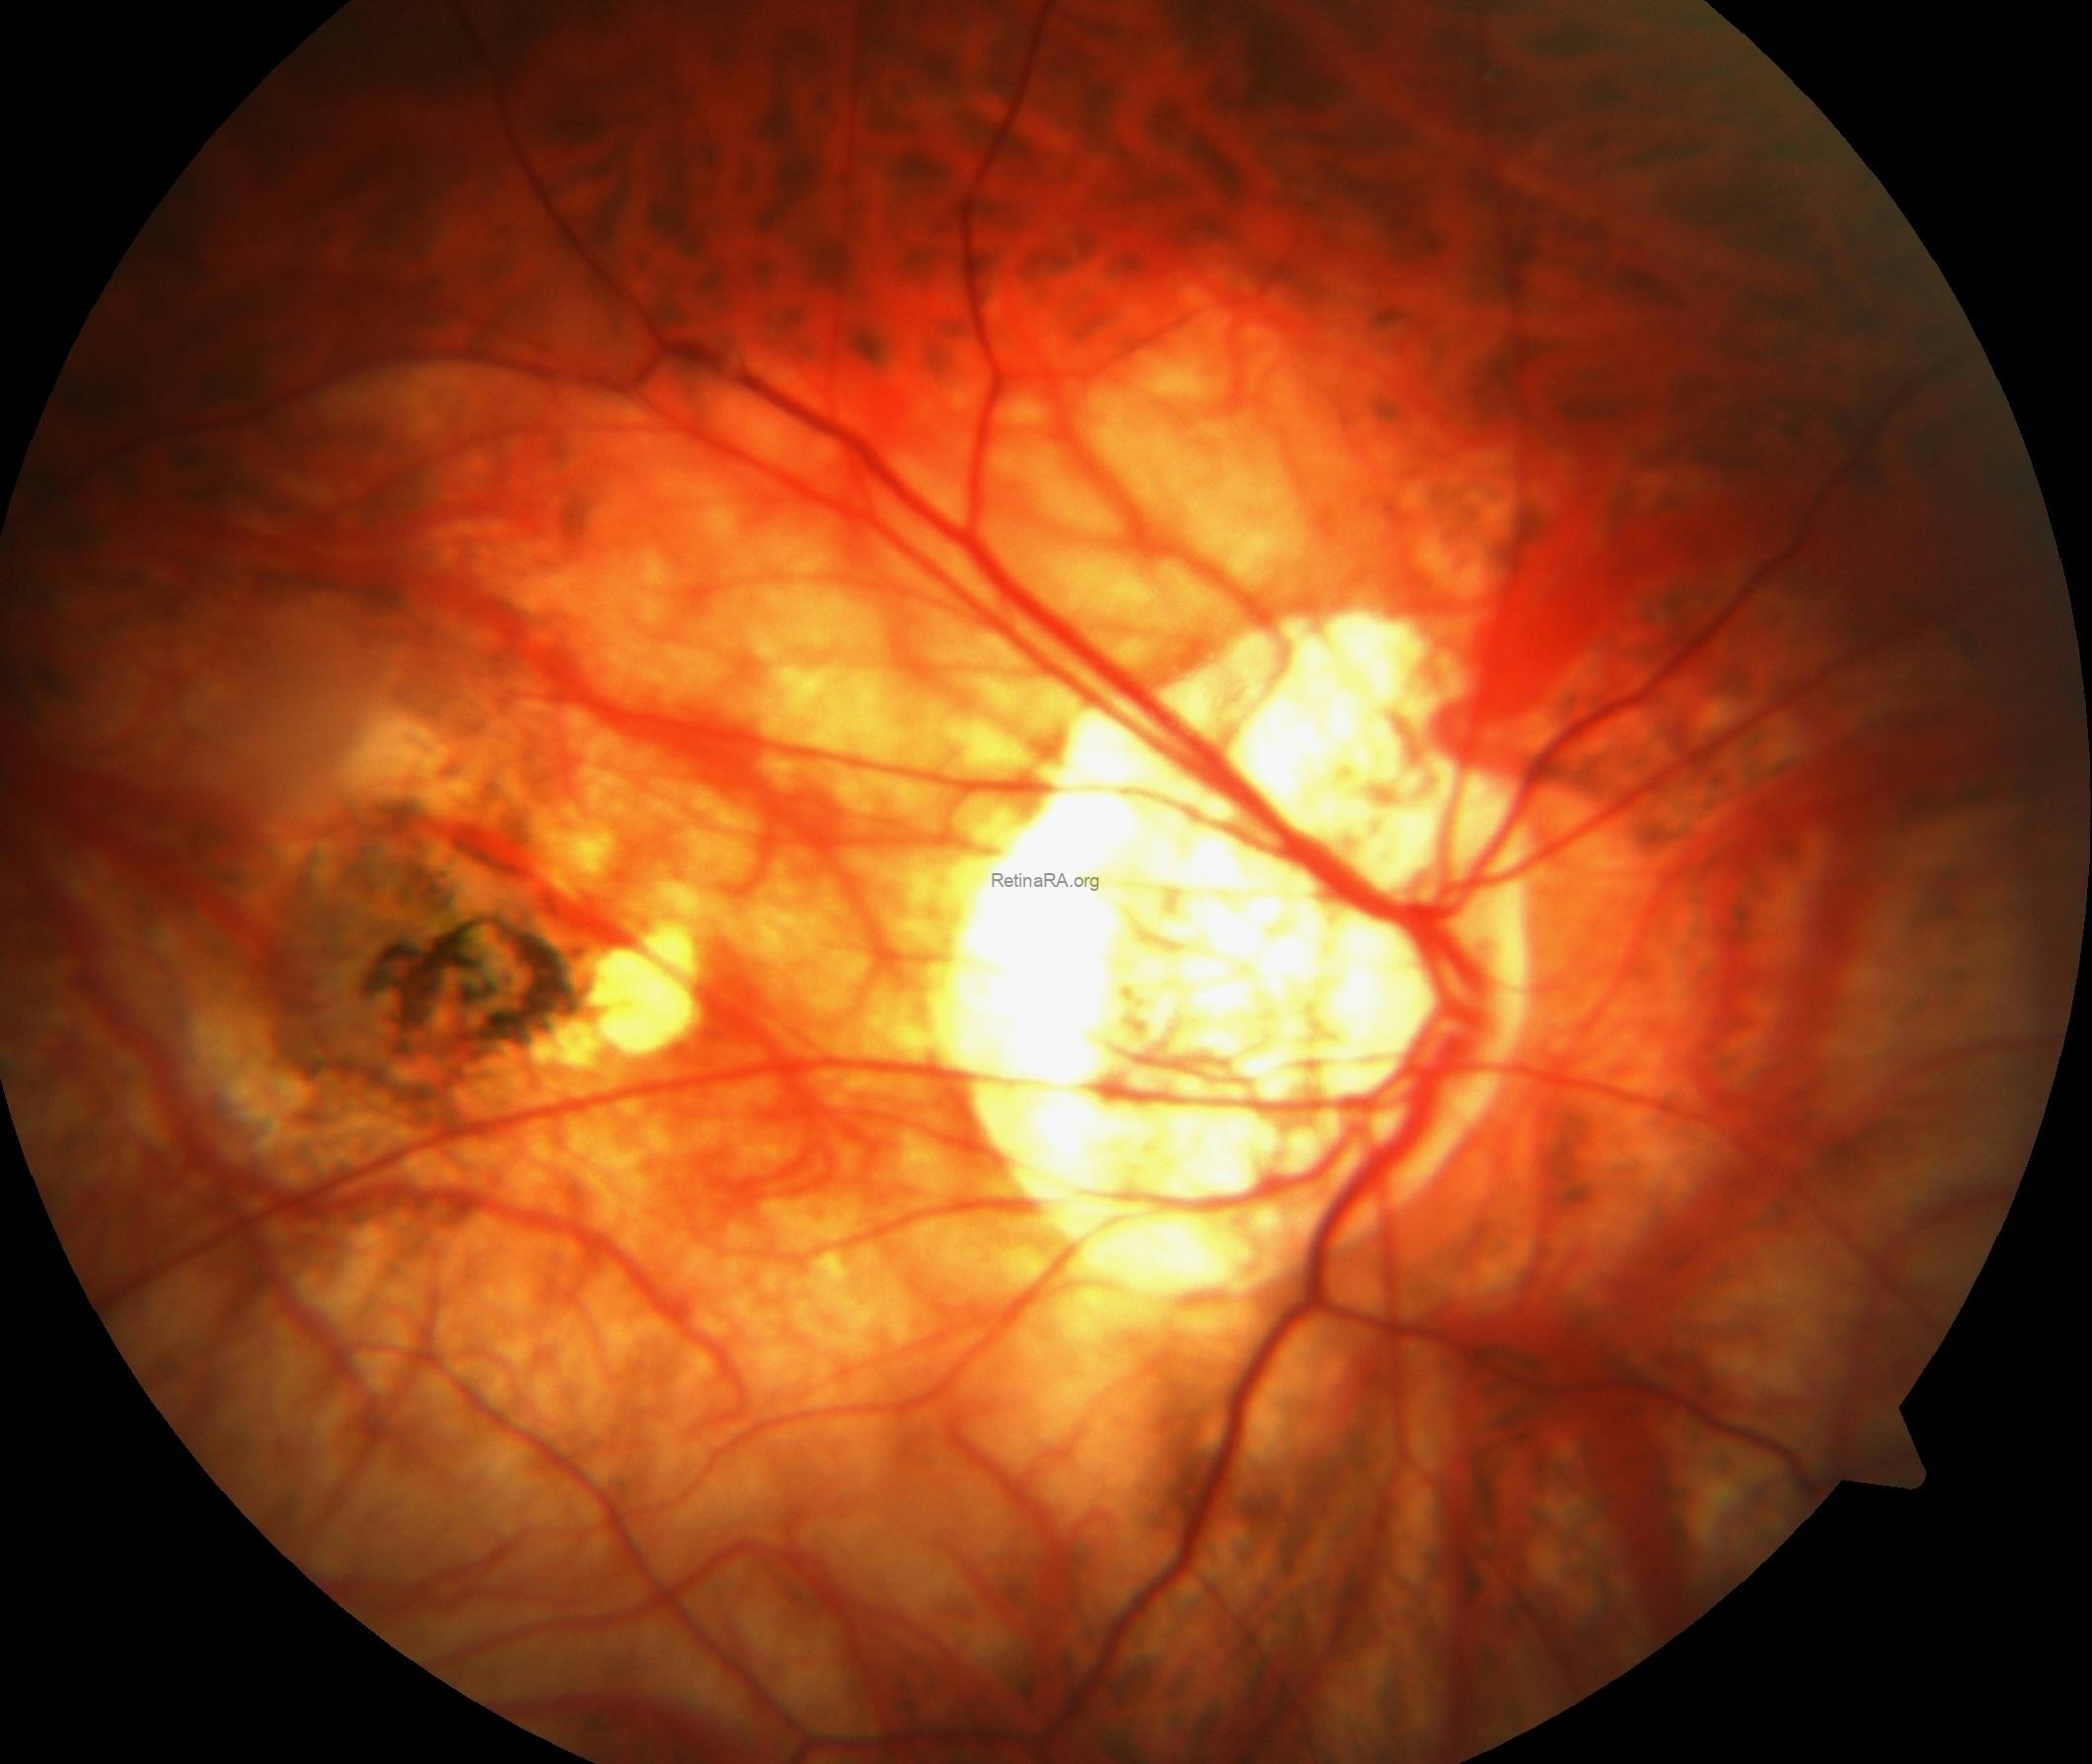

Dilated fundus examination of the right eye showed tilted disc, peripapillary and chorioretinal atrophy as well as macular scar, while the left eye exhibited aa well-defined, yellow-orange lesion located inferiorly along the border of the myopic crescent in additon to tilted disc, peripapillary and chorioretinal atrophy.

Spectral-domain optical coherence tomography showed the choroidal neovascular membrane scar without any subretinal or intraretinal fluid in additon to posterior staphyloma in the right eye. For the left eye, the OCT-scan passing throught the lesion under the optic disc exhibited an intrachoroidal space with a hyporeflective appearance below the normal plane of retinal pigment epithelium with normal Bruch’s membrane and retinal layers over the lesion.

Fundus fluorescence angiography showed scar staining without leakage in the right eye, while the peripapillary lesion in the left eye appeared as hypofluorescent in the early stages of angiography and hyperfluorescent without leakage in the late stages.